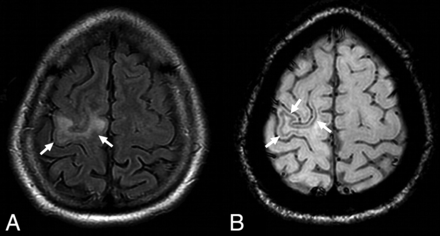

A 2016 study published in Radiology by Hodel et al27 investigated the radiologic findings of NTZ PML at the asymptomatic stage. They concluded that hyperintensity on DWI and involvement of U-fibers were the most predictive MR imaging features for the diagnosis of asymptomatic NTZ PML. Their results also suggested that punctate lesions may be a highly specific finding for NTZ PML, being exclusively observed in patients with NTZ PML. Most of the lesions observed in their study involved the frontal lobe as has been previously reported in other studies.28 They also found that comparison of the patient's current MR images with those from previous MR imaging examinations significantly improved the specificity for the detection of NTZ PML lesions and for the diagnosis of PML (from 88% without to 100% with previous MR imaging; P = .05). Recent evidence also suggests that SWI may be of value in the early diagnosis of PML (Fig 2). In particular, low signal intensity observed in U-fibers identified with SWI has been reported as a unique finding in early PML.33,34 Most interesting, the rate of PML in patients treated for <1 year remains virtually zero. Thus, the patient's length of treatment with natalizumab should be provided to the radiologist when interpreting MR imaging findings.

A typical example of natalizumab-associated PML. There is a FLAIR hyperintense lesion involving the right precentral gyrus (A, arrows) abutting the cortex. The susceptibility-weighted sequence reveals a hypointense rim involving the subcortical U-fibers adjacent to the PML lesion (B, arrows). Reprinted from Hodel et al.34